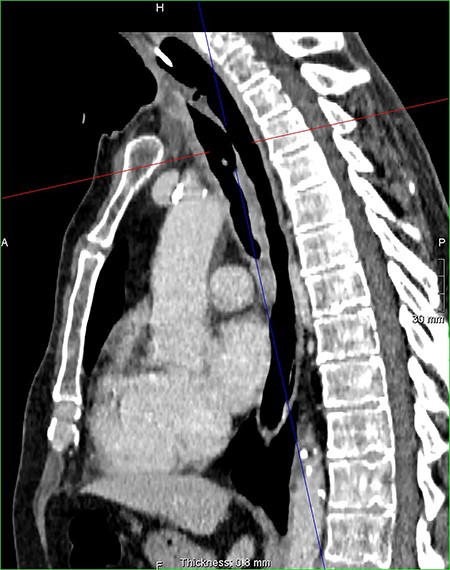

On examination, the patient had no obvious abnormality in the valve puncture. The stoma site was normal except for some crusting around the edges. A marked abnormality on the tracheal wall ~6 cm inferior to the stoma site was revealed, through a flexible nasal endoscopic examination. The abnormality was later confirmed to be a TOF. The patient underwent a computed tomography (CT) scan to delineate the surrounding anatomy as to facilitate the planning of the surgery (Figs 2–4).

Sagital reconstruction post contrast CT neck and thorax images with 4 mm defect/tracheoesophageal fistula located 8–9 cm from tracheostomy level and 12 cm proximal to the carina.